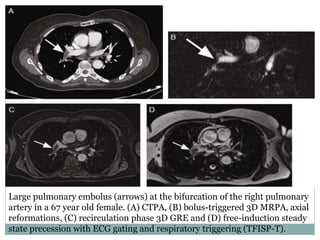

Large pulmonary embolus (arrows) at the bifurcation of the right pulmonary

artery in a 67 year old female. (A) CTPA, (B) bolus-triggered 3D MRPA, axial

reformations, (C) recirculation phase 3D GRE and (D) free-induction steady

state precession with ECG gating and respiratory triggering (TFISP-T).